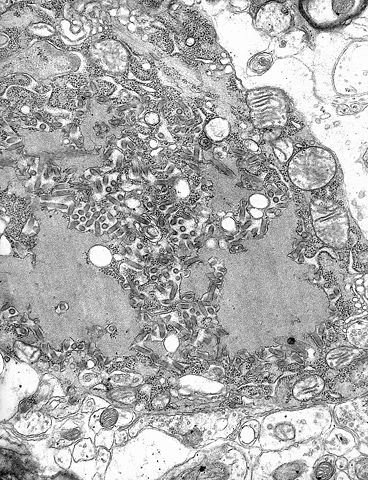

ID#: 1876 Description: Electron micrograph of the Rabies Virus. This electron micrograph shows the rabies virus, as well as Negri bodies, or cellular inclusions. Content Providers(s): CDC/Dr. Fred Murphy Creation Date: 1975 Copyright Restrictions: None - This image is in the public domain and thus free of any copyright restrictions. As a matter of courtesy we request that the content provider be credited and notified in any public or private usage of this image. |